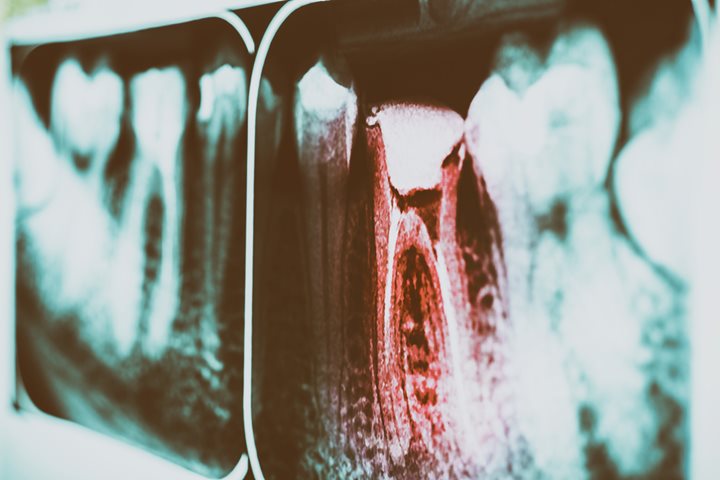

Tooth decay, also known as dental caries or cavities, occurs when bacteria inside your mouth create acid that eats holes in the surface layer of your teeth, or the enamel. As time goes by, this decay can grow larger if it’s left untreated and can eventually reach the nerve...

Tooth decay can happen to the best of us, but educating yourself on this potentially painful dental condition can help you prevent it in the first place. Here are seven important terms that relate to tooth decay: Cavities Cavities are holes in the teeth caused by tooth decay. Left...